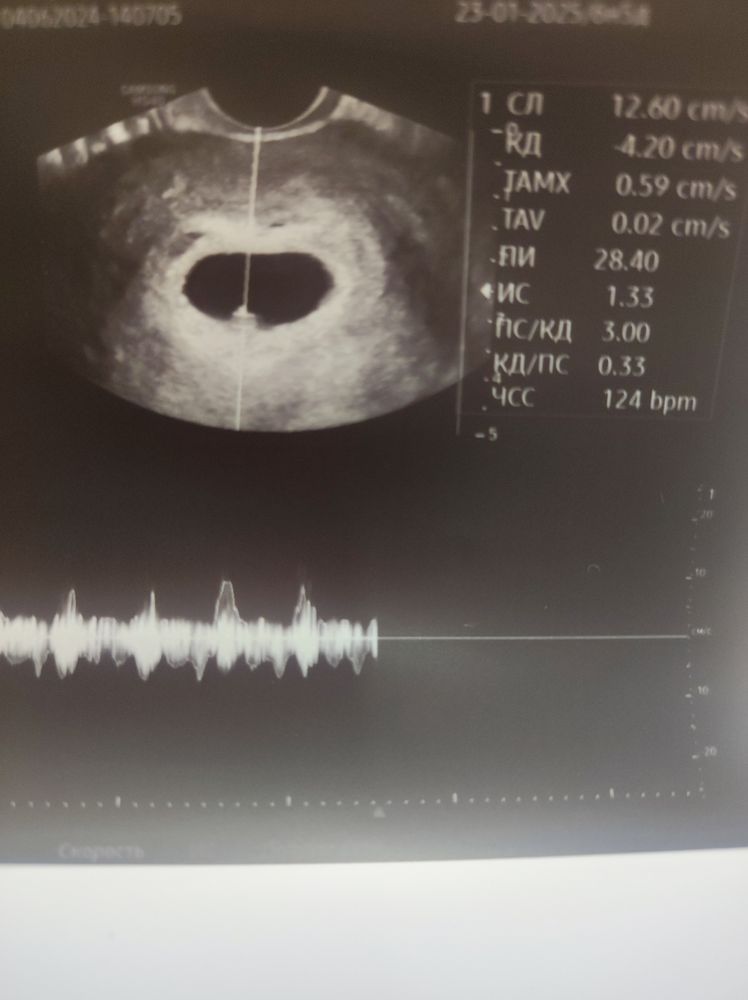

Нарушение кровотока 2 степени. Шейка 24 мм в первом триместре